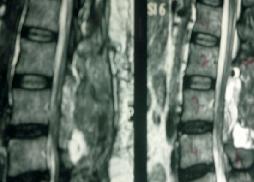

Large Conus Ependymoma